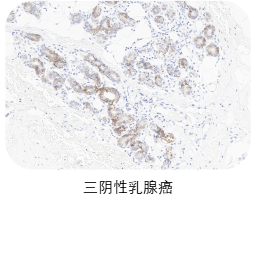

【IHC精准检测】——三阴性乳腺癌伴随诊断关键抗体:TROP-2

TROP2因其偶联药物“戈沙妥珠单抗”获批用于治疗三阴性乳腺癌而被越来越多的人所熟知。ADC药物开发成功的关键在于选择单克隆抗体特异性识别的靶点,TROP2在多种恶性肿瘤中均发生过表达,是单抗、ADC药物开发的首选靶点。

★ 验证充分:三阴性乳腺癌、前列腺癌、胰腺癌、卵巢癌、皮肤癌临床样本充分验证

❷ 适应症癌种染色

选取肿瘤组织样本用于敏感性染色,TROP2一抗染色阳性细胞细胞质和/或细胞膜特异性阳性着色(染色强度≥1),无非特异性着色(染色强度<1),无背景染色(染色强度<1 )。

ACRO IHC实验室目前已建立了成熟的TROP2染色方法与判读体系,适用三阴性乳腺癌、前列腺癌、胰腺癌、卵巢癌、皮肤癌等多个癌种,可快速用于相关肿瘤的临床试验入组筛选与样本检测,部分结果展示如图所示。